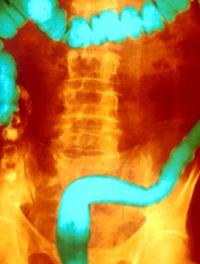

L'intestin moyen s'étend de la racine de l'anse duodénale au tiers inférieur du côlon transverse. Il se compose notamment du duodénum [...]